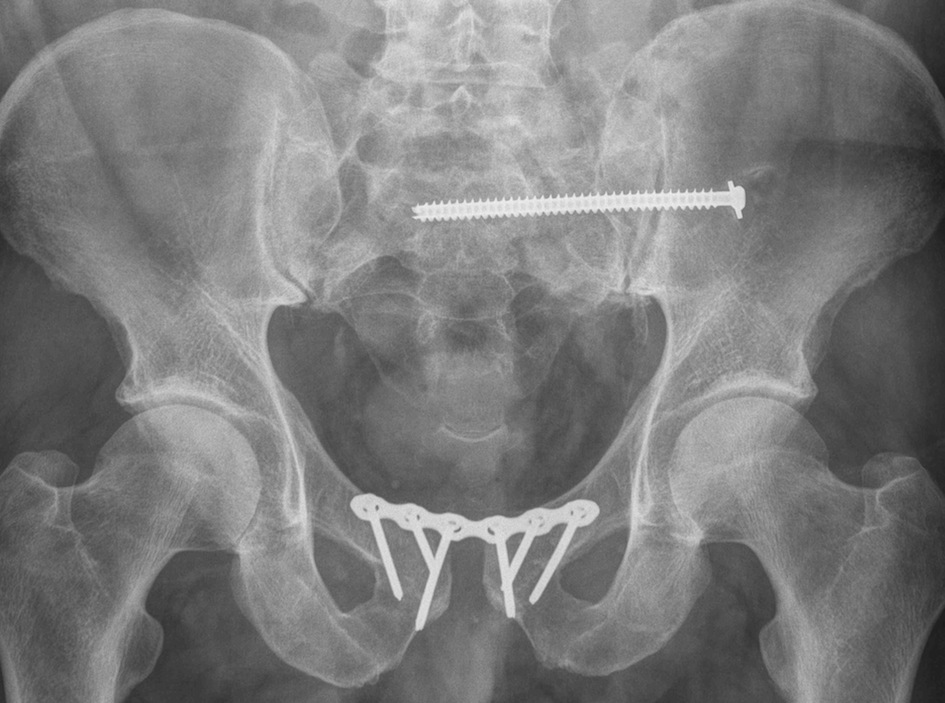

Superiorly applied plate

- pelvic reconstruction plate

Post-operative XRs: AP, outlet and inlet views

Outcomes of pubic symphysis plating

- 148 patients with pubic symphysis plating

- hardware breakage in 63 patients

- 60% of these patients asymptomatic

- 5 patients required revision for failure of fixation or symptomatic instability

Tseng et al Arch Orthop Trauma Surg 2022

- 9 patients with implant failure including plate breakage

- no difference in functional outcomes

- 58 patients with APC fractures treated with anterior plate versus anterior external fixation

- Majeed score of 70 with external fixation

- Majeed score of 79 with plate

- non significant